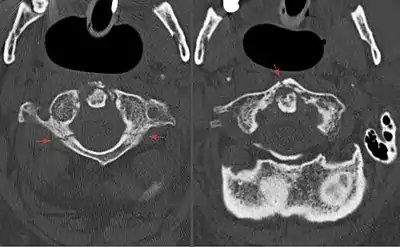

Jefferson fracture

A Jefferson fracture is a bone fracture of the anterior and posterior arches of the C1 vertebra,[1] though it may also appear as a three- or two-part fracture. The fracture may result from an axial load on the back of the head or hyperextension of the neck (e.g. caused by diving), causing a posterior break, and may be accompanied by a break in other parts of the cervical spine.[1]

Diagnosis